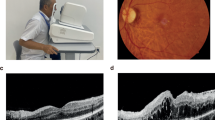

To present and validate a deep ensemble algorithm to detect diabetic retinopathy (DR) and diabetic macular oedema (DMO) using retinal fundus images.

A total of 8739 retinal fundus images were collected from a retrospective cohort of 3285 patients. For detecting DR and DMO, a multiple improved Inception-v4 ensembling approach was developed. We measured the algorithm’s performance and made a comparison with that of human experts on our primary dataset, while its generalization was assessed on the publicly available Messidor-2 dataset. Also, we investigated systematically the impact of the size and number of input images used in training on model’s performance, respectively. Further, the time budget of training/inference versus model performance was analyzed.